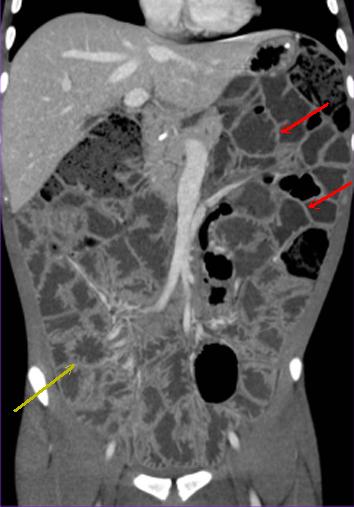

| Epaissisement parietale avec

oedeme de la sous muqueuse ( fleche rouge ) . Image

de fissuration legere peut se voyait un peut dans ce

cas . Maladie de Crohn de ileon en coupe TDM

coronale |

Signe de peigne " comb

sign " ( fleche jaune ) et epaissisement de la paroi

de ileon . Maladie de Crohn en phase aigue . Image

TDM . |